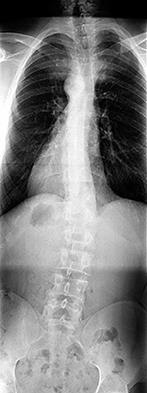

A 25-yo man sustains the injury shown in Figures 29a and 29b as a result of high-speed trauma. Examination reveals diffuse weakness in the lower extremities that is slightly worse on the right side, and decreased rectal tone and sensation. A CT scan is shown in figures 29c and 29d. Definitive treatment of the injury to the spine is delayed because of a severe pulmonary contusion. At 15 days after the injury, the patient’s neurological status remains unchanged. Management should now consist of